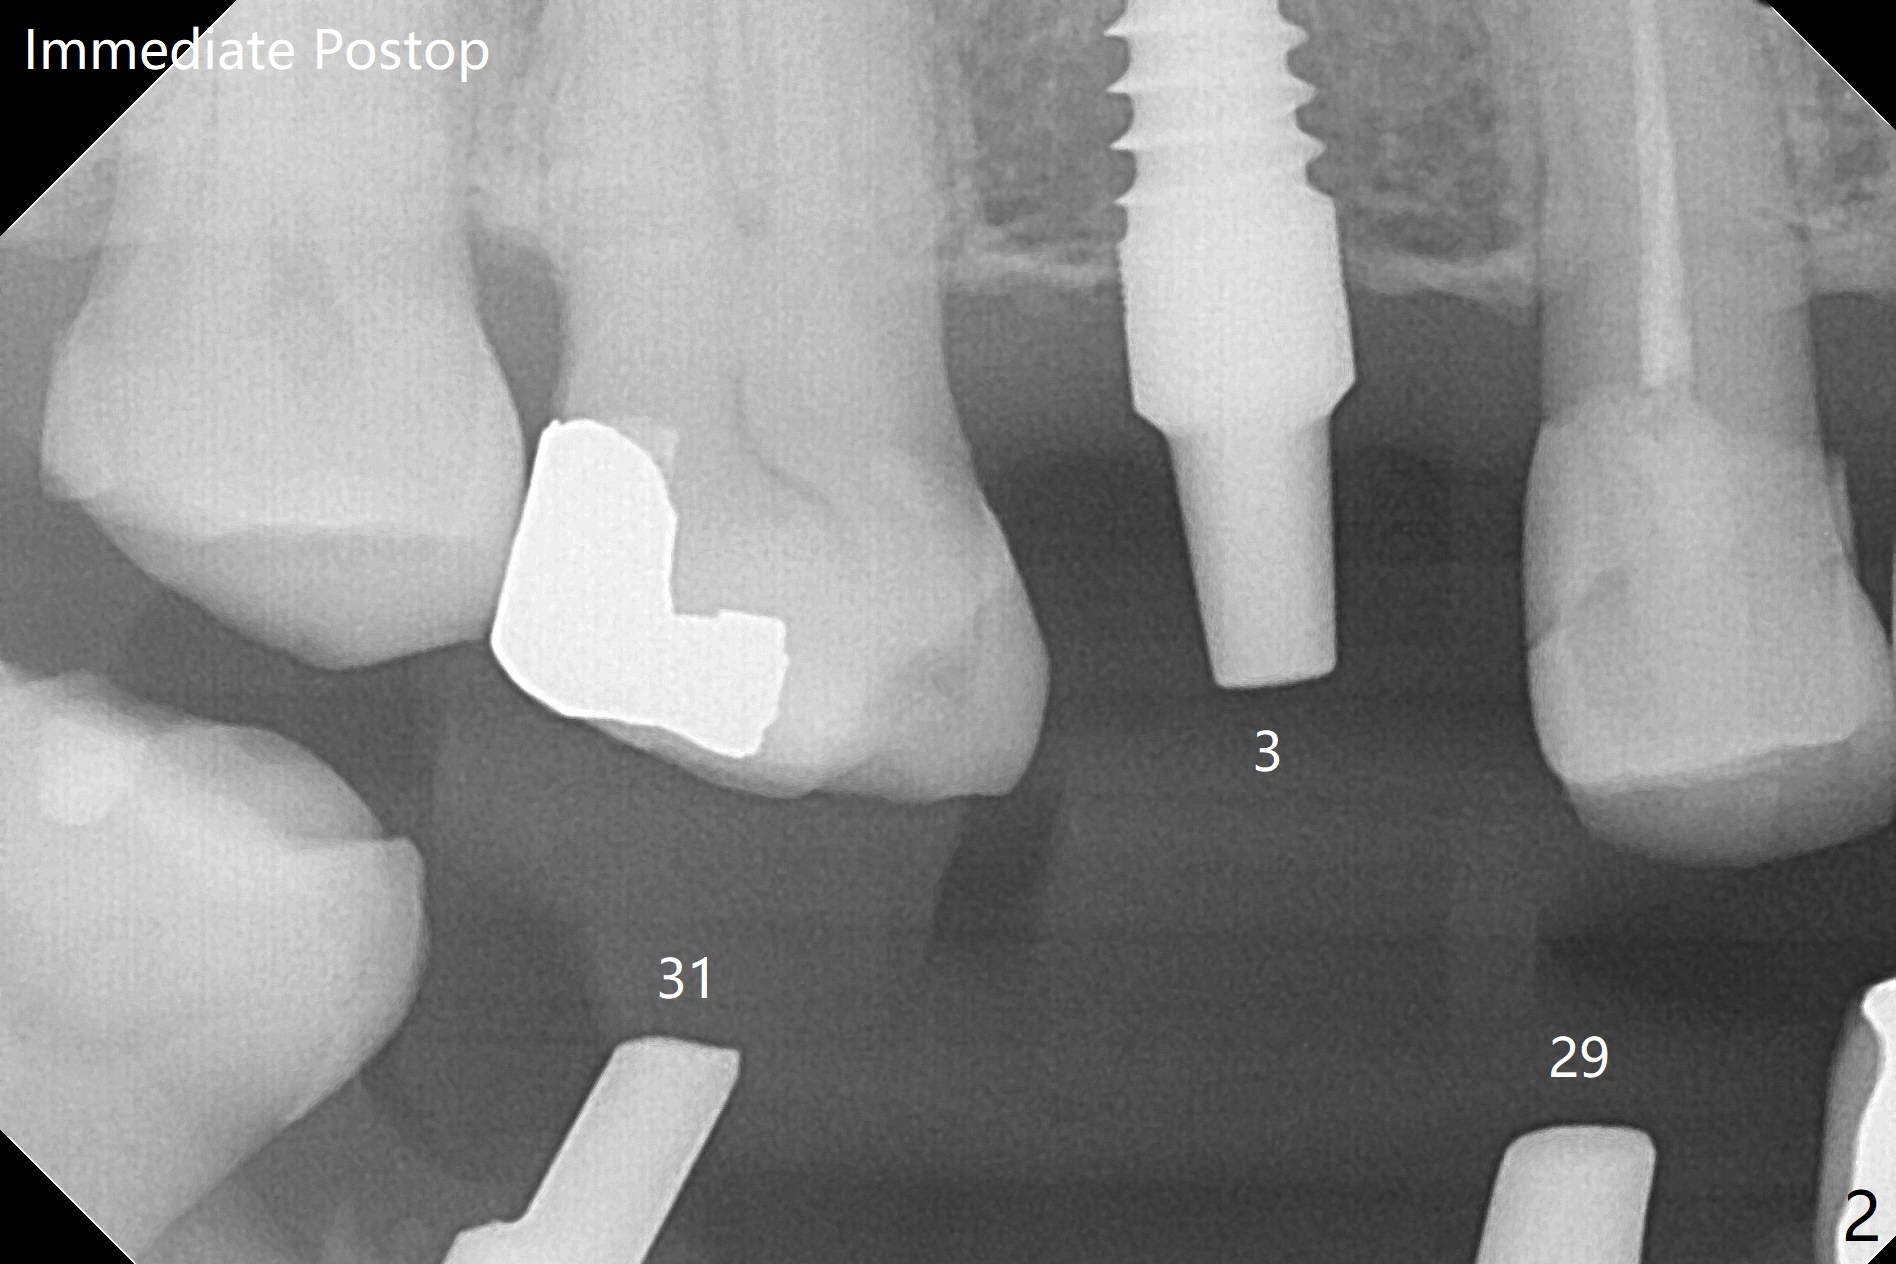

81岁女缺失3,29-31号牙,准备在3,29,31位点种植,大约术后3-4个月做3牙冠,29-31桥。为了简化治疗,选择一段式植体,牙槽嵴不宽裕。为了减少并发症,第一,植体有前后自然牙保护,第二,植体直径不是太小,第三,在导板指引下,植体方位基本正常(图一至四)。上颌缺牙区角化龈宽,使用环形刀,而下颌角化龈窄,切开种植,之后植骨(图四:箭头)。由于上颌骨质稀疏,上颌植体扭力低,暂时不做临时修复。为了降低植体微动,术后降低29,31基台高度(比较图三,图四)。最后利用基台固定牙周敷料。